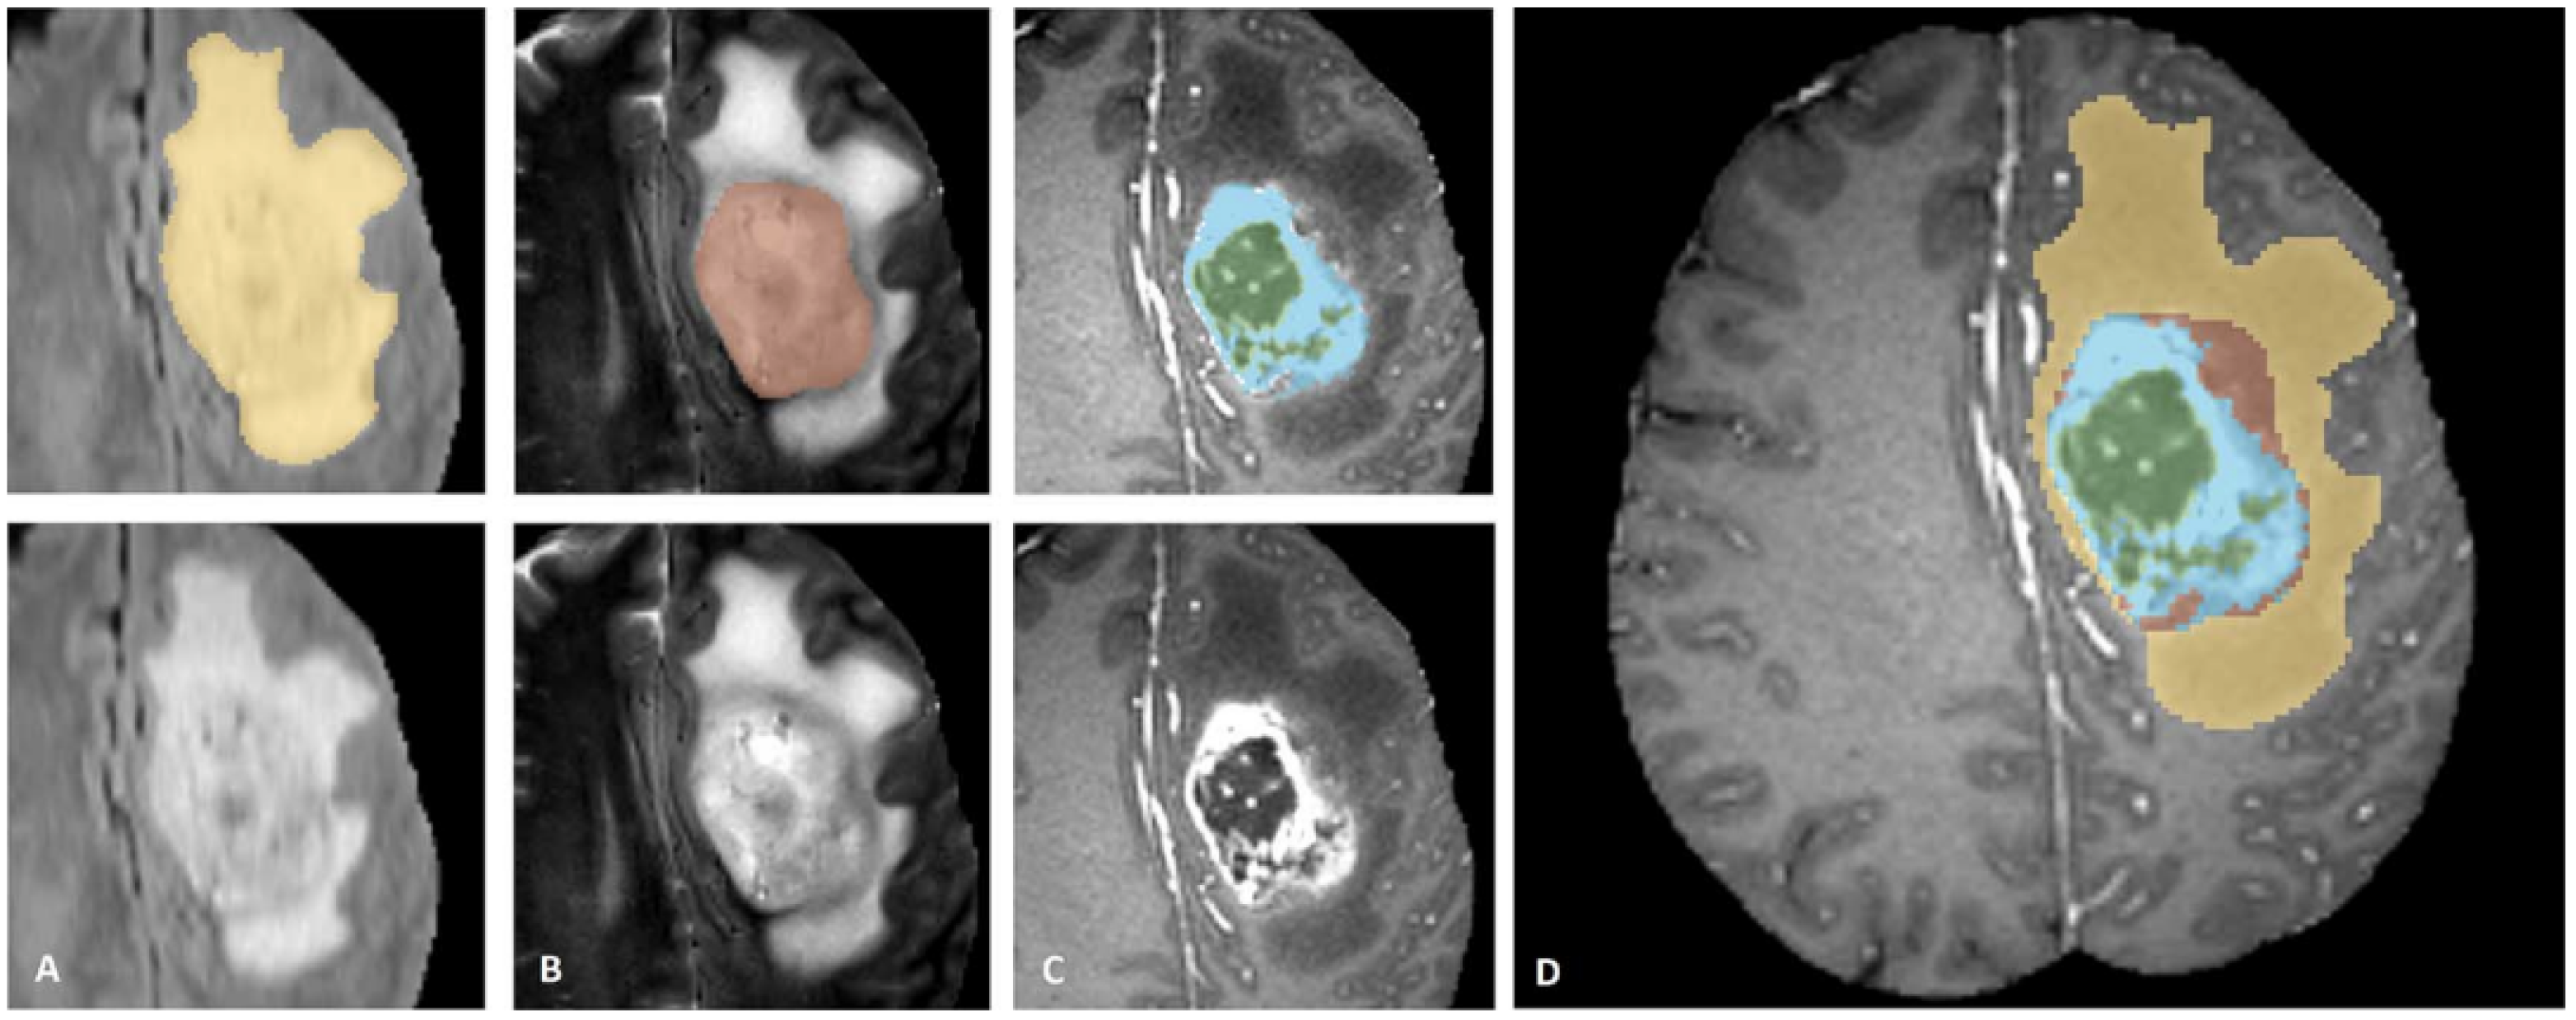

3.3. Segmentation